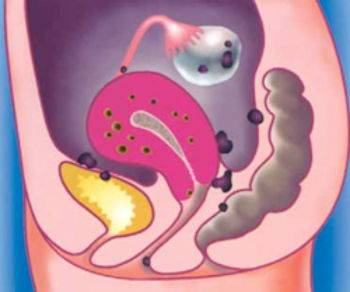

Внутренний генитальный эндометриоз (аденомиоз матки) — это гинекологическая патология, при которой эндометрий (ткань, выстилающая матку изнутри) прорастает в мышечный слой матки (миометрий). Заболевание диагностируется у женщин 25-40 лет. На начальной стадии развития генитальный эндометриоз склонен протекать бессимптомно. А при отсутствии качественного лечения болезнь может приводить к таким осложнениям, как бесплодие, кисты яичников, менструальные кровотечения и нарушения цикла.

Болезнь часто сочетается с другими формами эндометриоза, опухолями и кистами яичников, миоматозными узлами матки, эндокринологическими отклонениями. Заболевание требует проведения тщательной диагностики, так как для аденомиоза матки характерны симптомы, которые наблюдаются и при других гинекологических нарушениях.

- Невозможность зачатия. Аденомиоз провоцирует появление патологических изменений во всей репродуктивной системе женщины. Хронический воспалительный процесс часто приводит к развитию спаек в малом тазу. Все это препятствует наступлению беременности. У многих женщин внутренний эндометриоз протекает без каких-либо признаков, но именно из-за отсутствия беременности они обращаются за медицинской помощью и у них выявляется аденомиоз уже II или III степени.